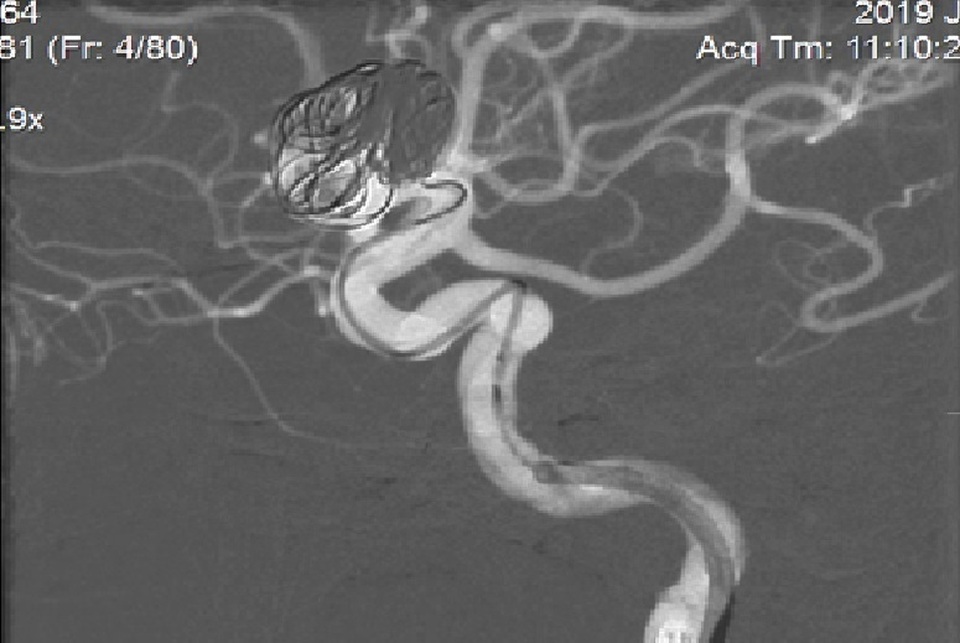

Đặt các vòng xoắn kim loại vào túi phình để tắc một phần túi phình